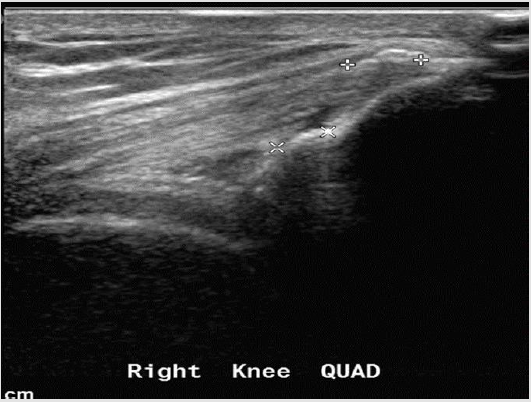

Figure 7: Quadriceps insertion tendinopathy - the quadriceps tendon appears hypoechoic with calcifications at its insertion into the patella.